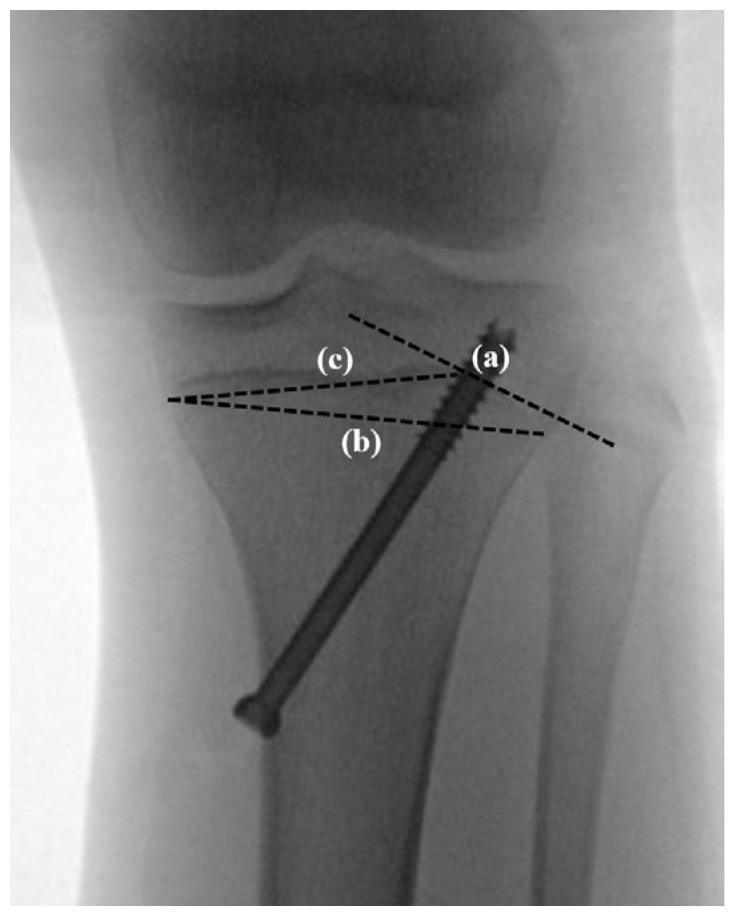

: To investigate postoperative courses after hemi-percutaneous epiphysiodesis using transphyseal screws (PETS) for genu varum. We especially focused on the degree of skeletal maturation that results in undercorrection. : We identified patients with idiopathic genu varum treated with hemi-PETS at the proximal tibia and followed-up to the completion of skeletal maturation. The acceptable correction was defined as the (1) final deformity < varus 1.0° or (2) final correction angle obtained by surgery (f-CA) > mean value of preoperative deformity. : In our cohort of 29 patients and their 29 lower limbs (one side was randomly selected in bilateral cases), the mean hip-knee-ankle (HKA) alignment was varus 6.5 ± 1.3° at the time of hemi-PETS. The mean f-CA was 5.8 ± 2.0° with a rebound of 0.3 ± 1.0°. Ten patients showed the finding of partial or complete fusion of the epiphysis of distal phalanges in the hand at the time of hemi-PETS (the fusion group, FG). Their f-CA was 4.0 ± 1.9° (with preoperative deformity of 6.9 ± 1.4°), which was significantly smaller than that (6.7 ± 1.3°, = 0.001) of remaining 19 patients (the open group, OG). The acceptable correction was obtained in all 19 patients of the OG. Otherwise, it was obtained in two patients in the FG ( < 0.001). The other two patients in the FG preoperatively showed a complete epiphyseal fusion of the distal phalanges in the hand, and their f-CA was 0.7 and 1.1°, respectively. : The degree of skeletal maturation corresponding to epiphyseal fusion of distal phalanges in the hand results in undercorrection after the hemi-PETS performed at the proximal tibia for genu varum.

: 研究经皮骺板螺钉(PETS)半骺阻滞术治疗膝内翻的术后过程。我们特别关注导致矫形不足的骨骼成熟度程度。 : 我们确定了接受经皮骺板螺钉半骺阻滞术治疗特发性膝内翻的患者,并随访至骨骼成熟完成。可接受的矫正定义为(1)最终畸形<1.0°或(2)手术获得的最终矫正角度(f-CA)>术前畸形的平均值。 : 在我们的 29 名患者及其 29 条下肢(双侧患者随机选择一侧)队列中,半骺阻滞术时的平均髋膝踝(HKA)对线为内翻 6.5±1.3°。平均 f-CA 为 5.8±2.0°,反弹 0.3±1.0°。10 名患者在半骺阻滞术时手部末节指骨骨骺出现部分或完全融合(融合组,FG)。他们的 f-CA 为 4.0±1.9°(术前畸形为 6.9±1.4°),明显小于其余 19 名患者(开放组,OG)的 f-CA(6.7±1.3°, = 0.001)。OG 组的所有 19 名患者均获得可接受的矫正。而 FG 组仅 2 名患者获得(<0.001)。FG 组的另外 2 名患者术前手部末节指骨骨骺完全融合,f-CA 分别为 0.7°和 1.1°。 : 手部末节指骨骨骺融合所对应的骨骼成熟度程度导致经皮骺板螺钉半骺阻滞术治疗膝内翻后矫形不足。